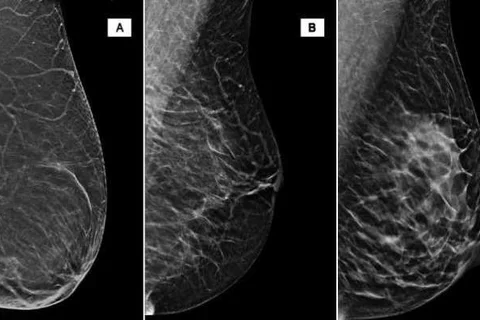

Women who have dense breasts and without other breast cancer risk factors should not be considered at high risk for breast cancer. Supplemental screening for breast cancer (breast MRI or ultrasonography) should be based on comprehensive risk assessment (not breast density alone) and should include patient’s values regarding the benefits and risks of additional tests and interventions.